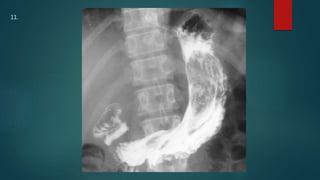

This document appears to be a medical report discussing several patients. It mentions a 35-year-old who was in a severe motor vehicle accident and an 81-year-old with a history of a non-vegetarian diet who had a perforated bowel from a chicken bone. The document provides few other details across its 25 numbered entries and was authored by Dr. Anish Choudhary for junior year 3 on May 30, 2016.